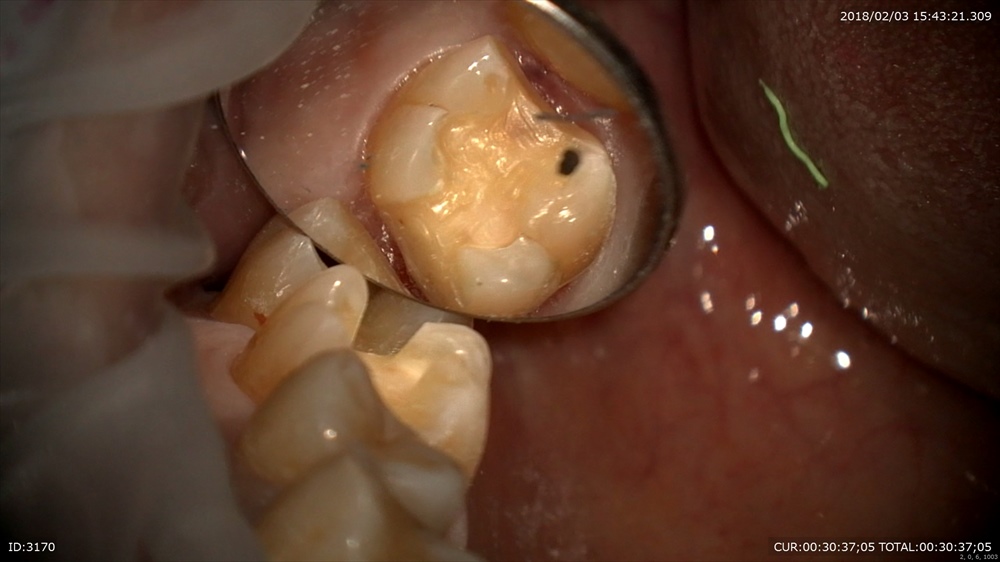

次はこの虫歯

歯と歯の間

すごいね。丁寧に感染を染め出して

MTAセメント